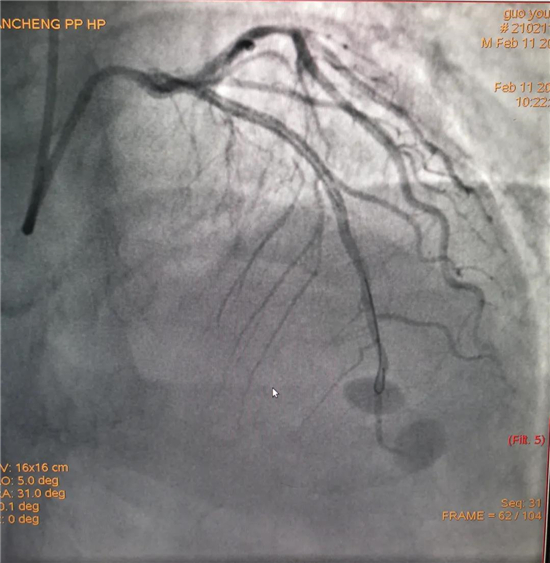

除夕,郭先生無明顯誘因突發(fā)胸痛,120急救人員到達(dá)現(xiàn)場(chǎng),心電圖顯示:竇性心律完全性束支傳導(dǎo)阻滯。信息立刻發(fā)送到胸痛中心介入微信群中,心內(nèi)科值班醫(yī)生初步診斷為急性廣泛前壁心肌梗死,必須盡快進(jìn)行急診支架治療,開通血管。值班醫(yī)生電話指導(dǎo)院前治療,并立即啟動(dòng)胸痛綠色通道,24小時(shí)備班的介入治療團(tuán)隊(duì)立即到位,9:30患者被送到導(dǎo)管室行冠脈介入診療,9:40急診PCI手術(shù)隨之開始,冠脈造影檢查提示左前降支閉塞,植入支架,堵塞的血管被順利打通,患者癥狀緩解,手術(shù)非常成功,10:20患者被送往病房進(jìn)一步治療。